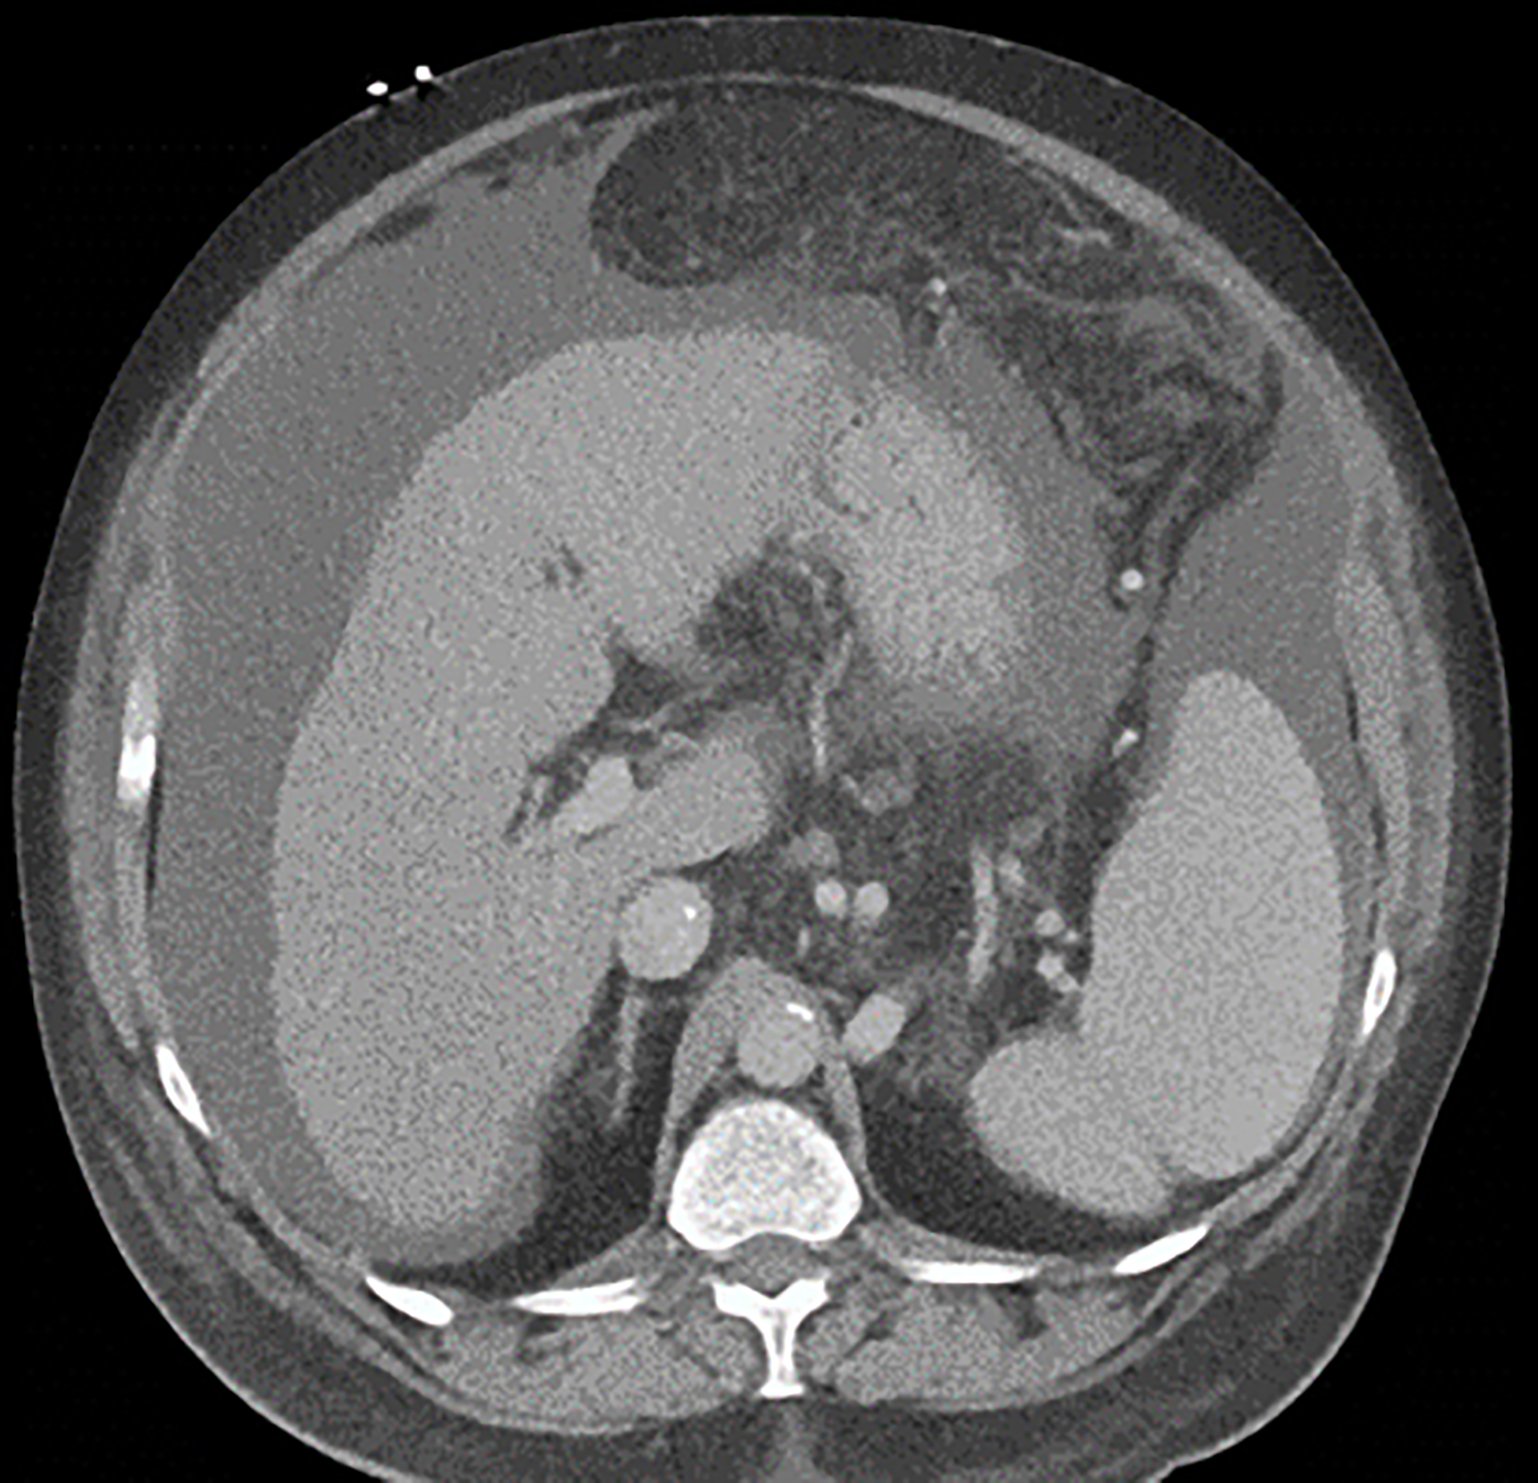

Endovascular coil embolization continues to become a more frequent modality of addressing hemorrhage and bleeding in patients. Migration refers to the coil unraveling or moving from the original embolization site. Migration of a coil is a known complication which can lead to serious consequences based on where the coil migrates. Despite increasing efforts to improve safety and technique, the risk of migration remains. We present a case of an embolization coil that migrated to the right ventricle, which was incidentally found roughly 2 months after undergoing an interventional radiology procedure for gastric variceal bleeding. The patient presented to the emergency department with dyspnea and abdominal pain. Unique images were obtained during his visit and in subsequent follow-up. As use of vascular embolization coils continues to become more commonplace, understanding the risks and complications of these procedures remains an important aspect of providing care for patients once they have left the interventional radiology suite. Coil migration should be a differential to consider in patients who present to the emergency department with signs or symptoms of arrhythmia or pulmonary embolism who have undergone a coil embolization procedure.